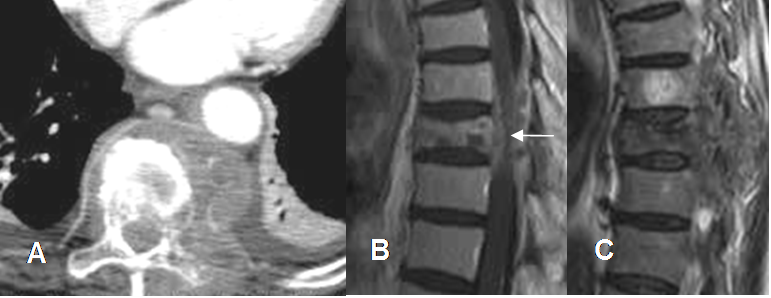

Fig 186. Linfoma.

A: TAC axial, B: RM sagital en T1 con contraste y C: RM sagital en T2. Cúmulo de adenopatías paravertebrales dorsales, con compromiso vertebral y masa de tejidos blandos que se extiende al canal modular. (Flecha).